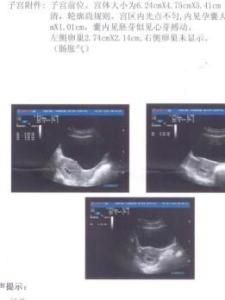

4周:胎兒只有0.2厘米。受精卵剛完成著床,羊膜腔才形成,體積很小。超聲還看不清妊娠跡象。

5周:胎兒長到0.4厘米,進入了胚胎期,羊膜腔擴大,原始心血管出現,可有搏動。B超可看見小胎囊,胎囊約占宮腔不到1/4,或可見胎芽。

6周:胎兒長到0.85厘米,胎兒頭部、腦泡、額面器官、呼吸、消化、神經等器官分化,B超胎囊清晰可見,並見胎芽及胎心跳。

7周:胎兒長到1.33厘米,胚胎已具有人雛形,體節已全部分化,四肢分出,各系統進一步發育。B超清楚看到胎芽及胎心跳,胎囊約占宮腔的l/3。

8周:胎兒長到1.66厘米,胎形已定,可分出胎頭、體及四肢,胎頭大於軀幹。B超可見胎囊約占官腔1/2,胎兒形態及胎動清楚可見,並可看見卵黃囊。

9周:胎兒長到2.15厘米,胎兒頭大於胎體,各部表現更清晰,頭顱開始鈣化、胎盤開始發育。B超可見胎囊幾乎占滿宮腔,胎兒輪廓更清晰,胎盤開始出現。

10周:胎兒長到2.83厘米,胎兒各器官均已形成,胎盤雛形形成。B超可見胎囊開始消失,月芽形胎盤可見,胎兒活躍在羊水中。

11周:胎兒長到3.62厘米,胎兒各器官進一步發育,胎盤發育。B超可見胎囊完全消失,胎盤清晰可見。